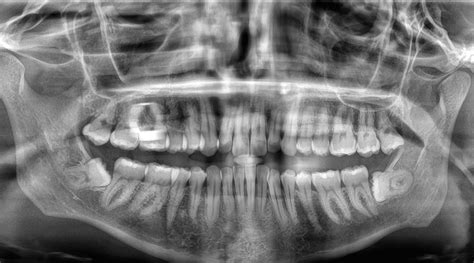

Las muelas del juicio, también conocidas como cordales, son piezas que suelen erupcionar en la adultez temprana y no siempre lo hacen de forma adecuada. Cuando la muela no ha salido del todo o está mal posicionada, puede inflamarse el tejido que la rodea. Esta inflamación provoca presión en los nervios cercanos al oído, lo que produce una sensación punzante o continua en esa zona. Las muelas del juicio causan dolor de oído especialmente si la infección ha avanzado a los tejidos blandos cercanos o si existe formación de pus.

Las infecciones en las muelas del juicio no aparecen de forma espontánea. Las muelas del juicio pueden infectarse por erupción parcial, falta de espacio o acumulación de bacterias y restos de comida que dificultan la limpieza. Al comer, hay alimentos que se retienen en esa bolsa, ya que la higiene no se realiza correctamente al ser una zona de difícil acceso.